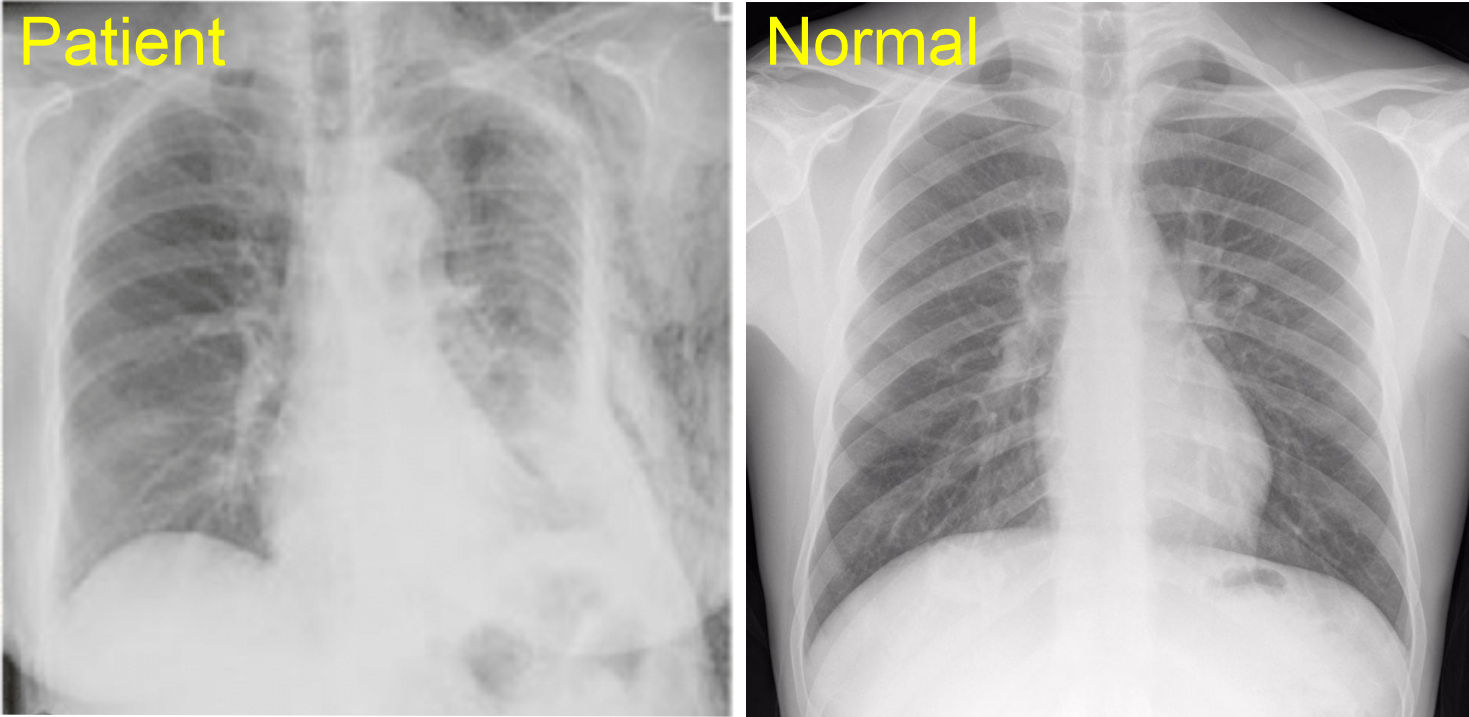

A patient was in a side car impact where the drivers side door collapsed inward impacting the anterolateral aspect of the patients left torso. The patient indicates they have extreme pain when moving their left arm and shortness of breath. The pain is significantly stronger than during quiet breathing. When moving the arm back and forth you hear a 'clicking' - Click here for sound - A chest film is ordered and shows

Question 1/3 - What are you concerned about?